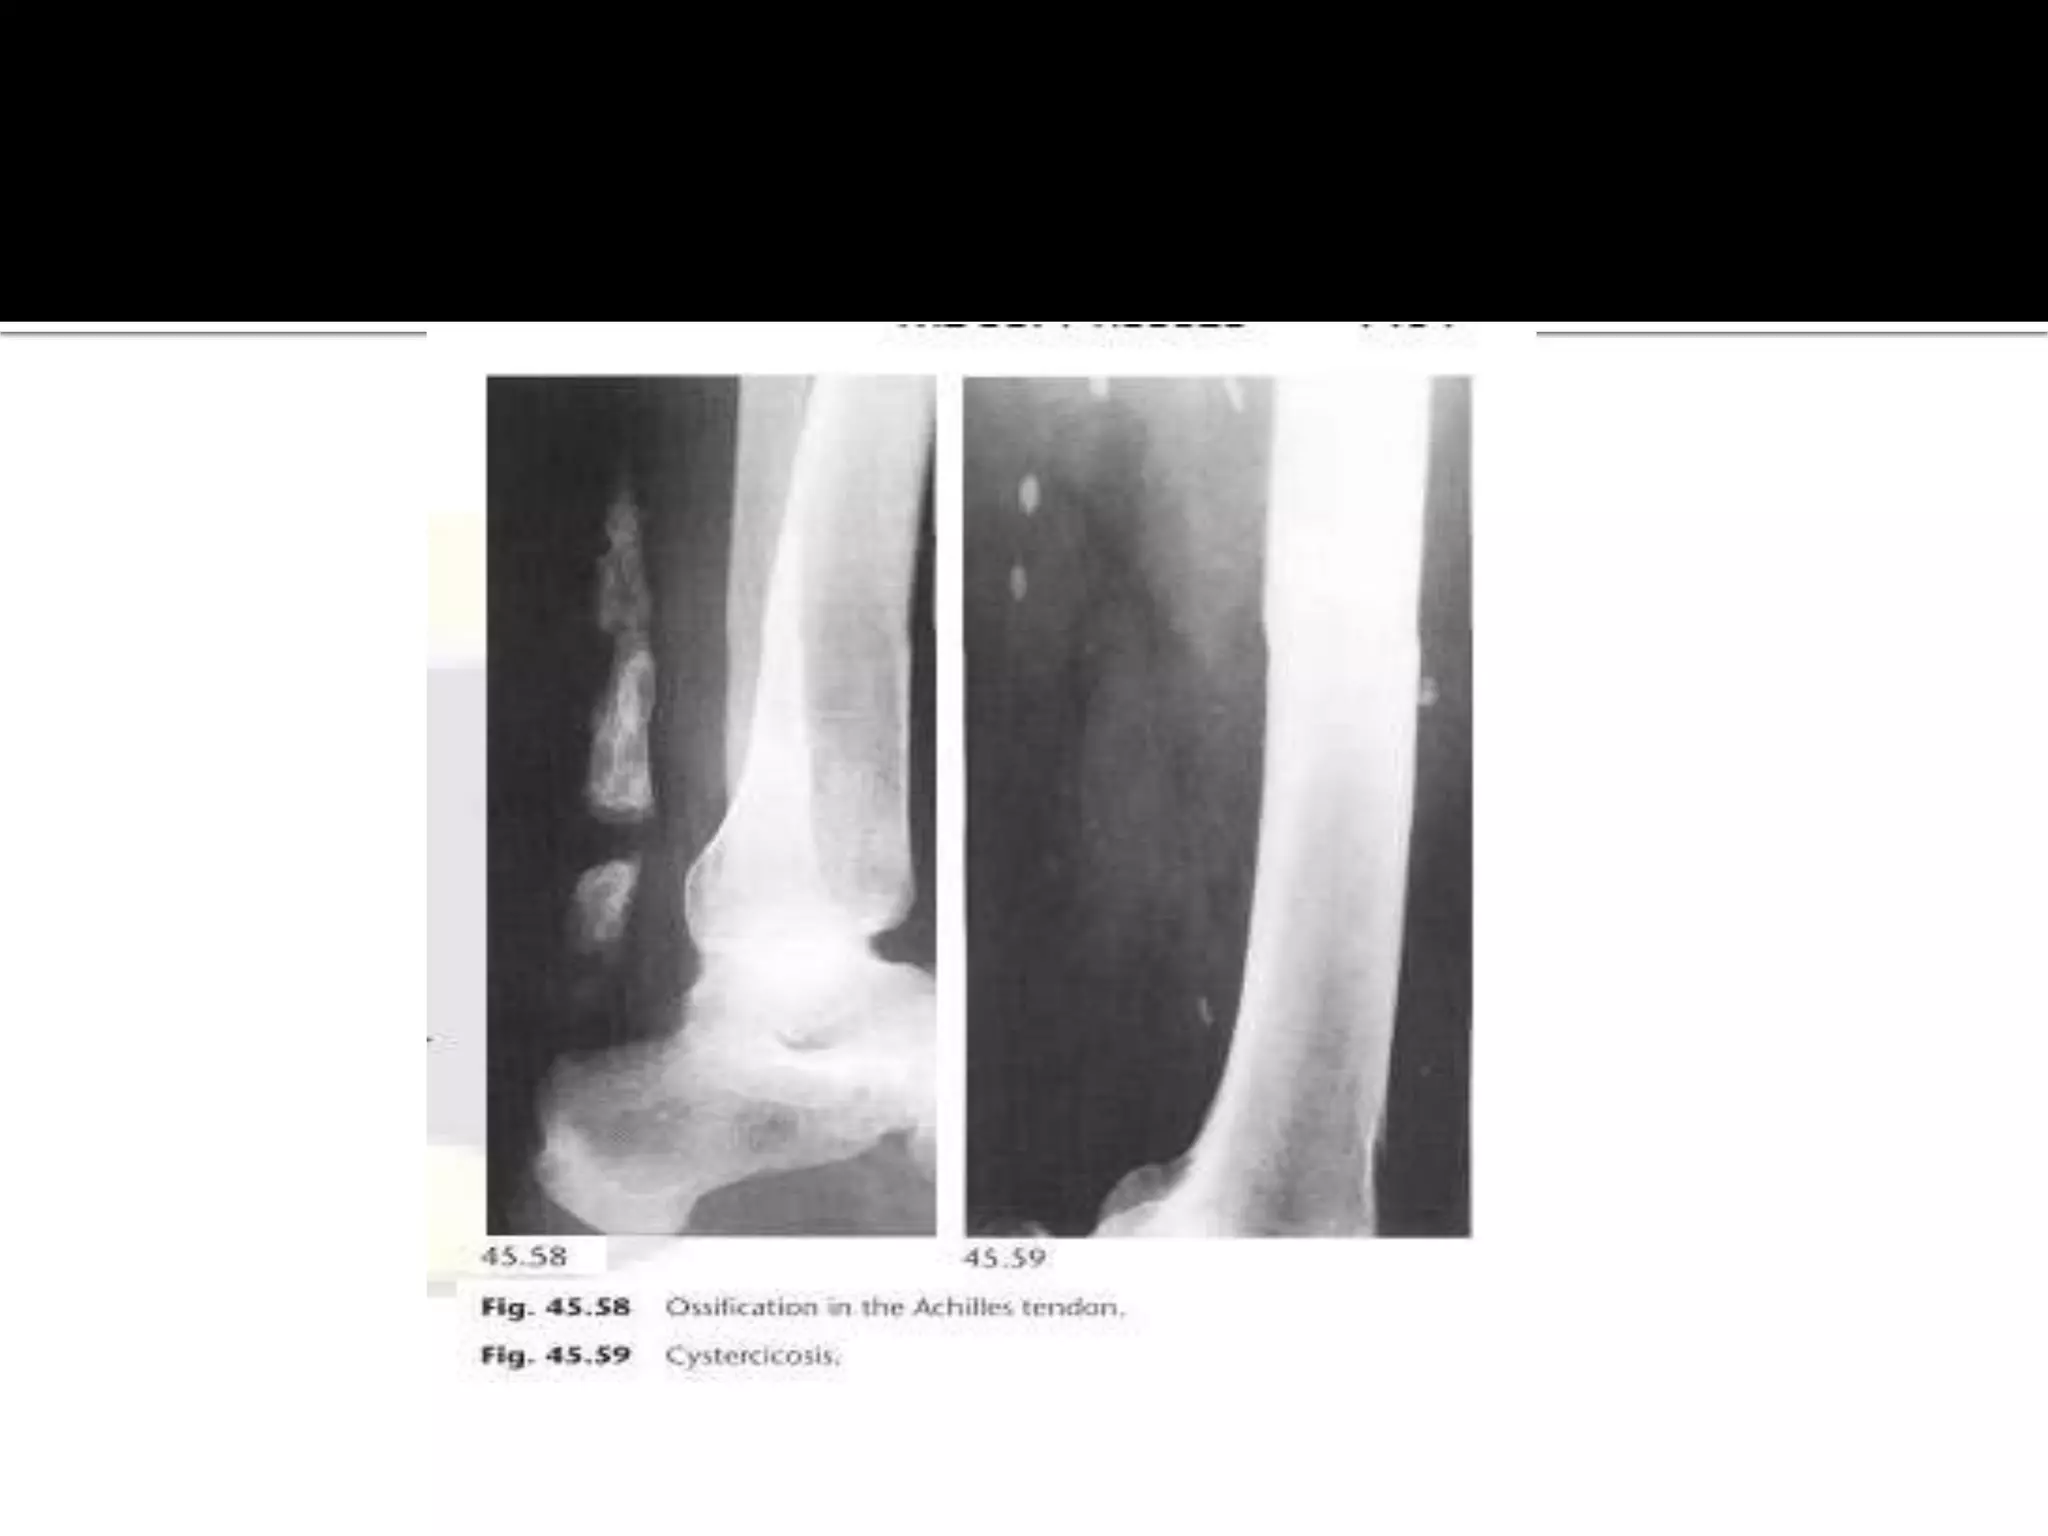

Calcification in tendons,patella,Achilles

 Due to chronic trauma or inflammation

Parasites

 Ova of the pork tape worm ,taenia solium are

ingested by eating under cooked infected meat with

the pig being the intermediate host.

 The embryo enters the blood stream and the

parasites ,cysticercosis cellulosa, becomes encysted

within the soft tissues ,brain and meninges.

 In muscles the parasites calcifies forming ellipsoids

masses 10-15 mm long often with a translucent

centre and which is lie in the direction of the muscle

fibers.

Calcification in tendons,patella,Achilles Due to chronic trauma or inflammation  Rotator cuff especially supraspinatus tendon most commonly affected  Calcification lies directly over the humeral head in crescentic distribution. it may be present symptomatic patents.

 In musclesthe parasites calcifies forming ellipsoids masses 10-15 mm long often with a translucent centre and which is lie in the direction of the muscle fibers.  The guinea worm Dracunculus medinensis dies in the muscles and forms a spherical calcified mass or a long string like calcified worm 10-12 cm in length.(India,Africa,Middle East)